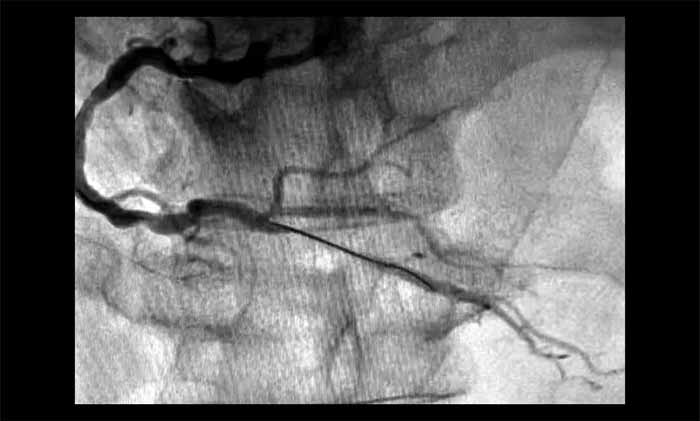

▲ 术后,血管顺利开通

1月28日,姜朝晖博士团队为患者行冠状动脉球囊扩张及支架植入。术中,行多角度造影提示RCA中段严重狭窄近95%,并伴有血栓。通过及时介入,开通闭塞血管,恢复了心肌供血。